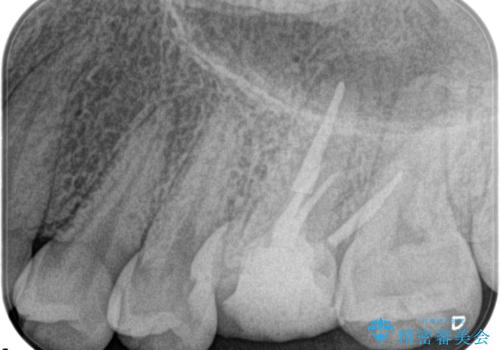

奥歯の根管治療

- 定期検診にて根尖に病変を認めた患者様です。

歯髄壊死の診断にて根管治療を行っております。

- 精密根管治療(イニシャルケース,大臼歯):122,000円、ファイバーコア:22,000円費用は治療当時の料金となります